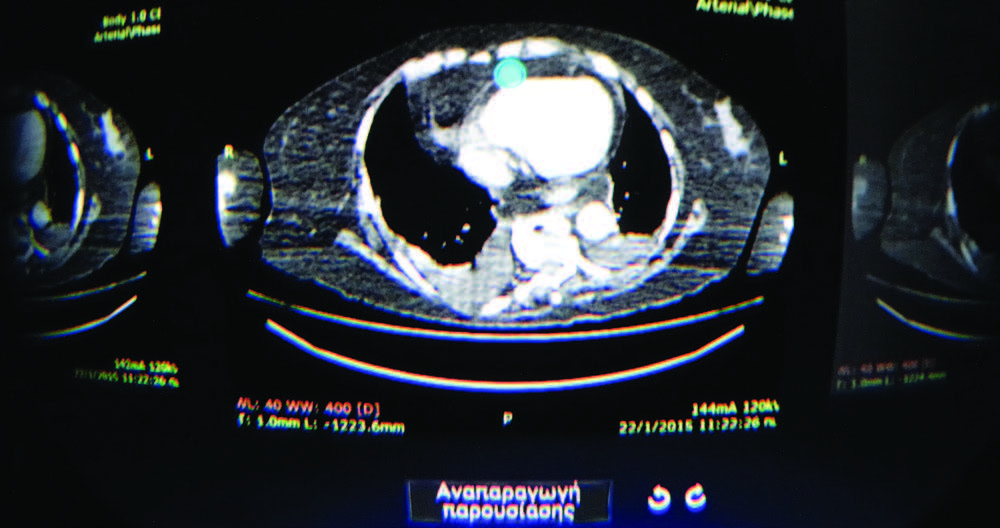

Using a high-resolution mobile virtualreality (VR) prototype, Vasileios Moustakas, M.D., of Evangelismos Hospital in Athens, Greece, and colleagues investigated whether VR visualization of Digital Imaging and Communications in Medicine (DICOM) images could be used without compromising image stability or quality, enabling its use for diagnostic imaging. A secondary purpose was to verify that remote diagnosis of complete CT examinations performed elsewhere, using a mobile VR system, was feasible.

The lightweight mobile VR system is powered by a high-tech Smartphone with an ultra-high-density 550 ppi display. Using the system is like being in front of a 175-inch mega screen while enabling visualization at 360 degrees, Dr. Moustakas said. Once the DICOM images are downloaded, the user wears the device and can scroll through the images, viewing up to 56 at any time—all while being on the move.

Even if the VR system can be used for DICOM images, researchers opted to test the device using CT images due to the modality’s heavy use in emergency departments. Once the VR system was ready, 271 exams were reviewed by a consultant radiologist in the hospital and by another radiologist using remote VR in another area who had contact with the first doctor. The two independent, double-blinded reports were compared using standardized reporting systems to assess imaging quality of the VR system in comparison to the hospital’s workstation.